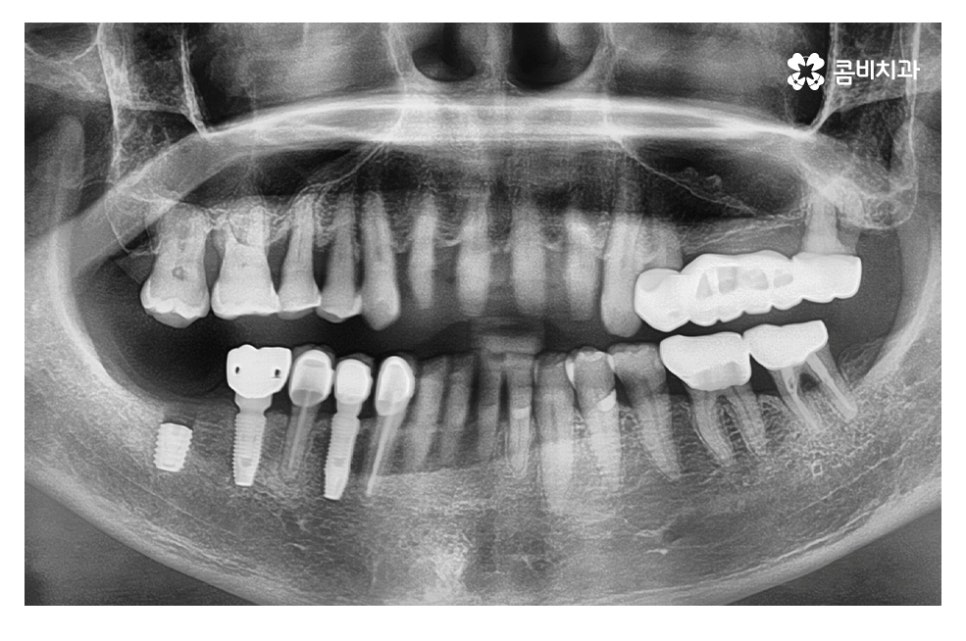

위 케이스의 경우 영구치가 손실된 상태에서 시간이

어느 정도 경과된 후 임플란트 수술을 진행하였으며,

영구치가 손실되고 어느 정도 뼈가 차있고, 현 상태에서

식립이 가능했기 때문에 뼈이식 없이 임플란트를 식립하였고

이때 골 유착 과정을 거치면서 임플란트가 단단하게 고정되고

치료가 마무리되면 자연치아에 버금가는 저작력을 갖추게 될 수 있어요.